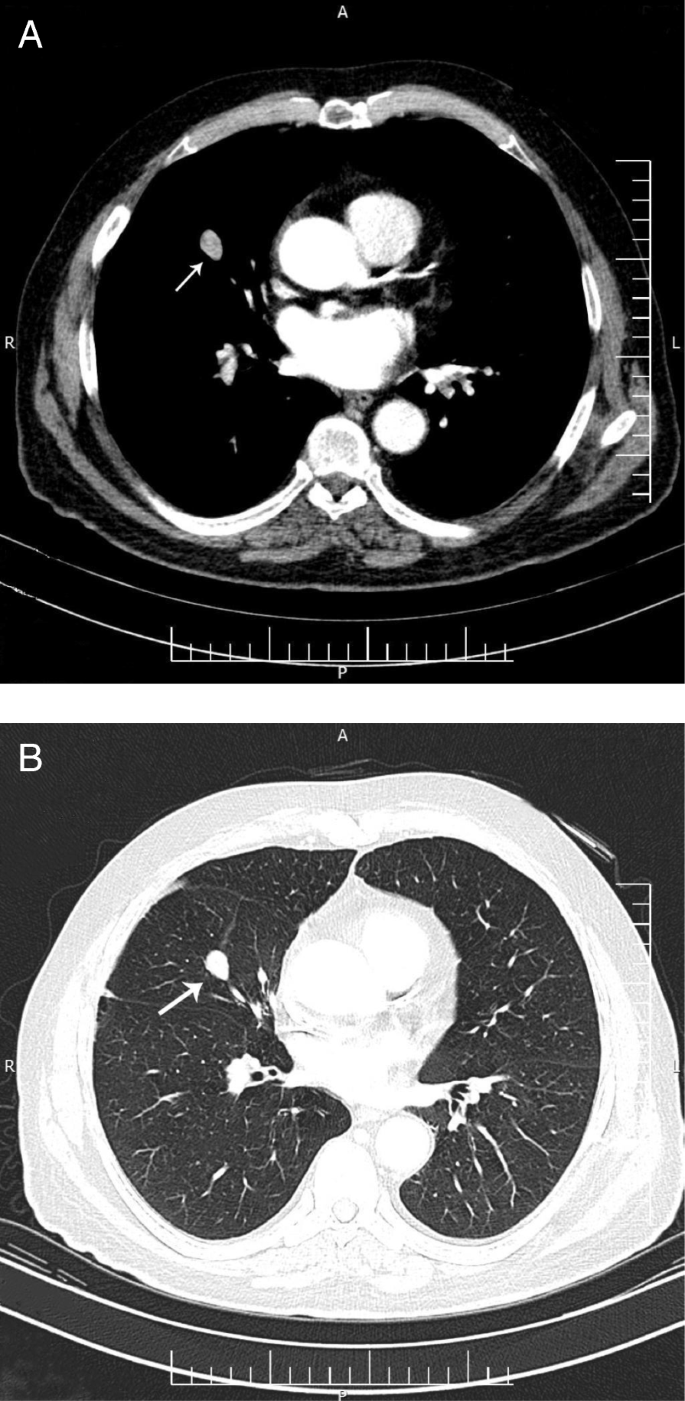

A 49-y-old man admitted to an emergency department in 21 December 2005, with the complaint of drowsiness and quadriparesia. On admission, the patient was afebrile and had a blood pressure of 200/110 mmHg, pulse rate of 95/min and, a body mass index of 32 kg/m2. On physical examination, he had facial plethora, central obesity, pitting edema of limbs, without evidence of purple striae or hyperpigmentation. On neurologic examination, cranial nerves function was intact, proximal and distal force were 3/5, and tendon reflexes were diminished. Other examination was unremarkable. His problem was started a year ago with weight gain (4 kg), fatigue, proximal muscle weakness, easy bruising and hypertension. He didn’t complaint paroxysmal hypertension, headache, palpitation, or sweating. He had been smoker of 20 pack/y for almost 30 years, with no previous medical or surgical history, and no family history for endocrine disease. Initial work up on admission revealed marked hypokalemia (2.1 mEq/L), metabolic alkalosis (pH: 7.58, HCO3:57.2 mEq/L) and blood glucose of 330 mg/dL. Electrocardiogram showed long QT interval (0.52 s), inverted T wave, and prominent U wave in precordial leads. The patient admitted in coronary care unit. According to high suspicious of CS, 24-h urine for urinary free cortisol (UFC) was collected. Laboratory data revealed UFC greater than 1000 μg/24 h (reference value: 50–149 μg/24 h), serum ACTH 257 pg/mL at 8 AM (reference value: 9–46 pg/mL), and morning serum cortisol 57 μg/dL (reference value:5.5–26.1 μg/dL) (Table 1). Following 8 mg oral administration of dexamethasone at 11 PM, no suppression was found at morning serum cortisol level (67 μg/dL). Considering ACTH-dependent CS, dynamic pituitary magnetic resonance imaging (MRI) was done that did not show pituitary adenoma; spiral chest and abdominopelvic computed topographies (CT) were unremarkable, except of the significant enlargement of bilateral adrenal glands. Treatment with ketoconazole, 200 mg every 12 h, was initiated to control hypercortisolism. According to persistent hypokalemia despite excess potassium supplement (> 120 mEq/day) 2 days after starting ketoconazole, the patient was scheduled for bilateral trans-abdominal open adrenalectomy on 28 December 2005. The weights and sizes of excised right and left adrenal glands were 18 g, 6× 3× 0.8 cm and 20 g, 6× 3.5× 1 cm, respectively. Microscopic examination revealed diffuse adrenocortical hyperplasia. Three days after surgery, 24-h UFC, morning serum cortisol and ACTH levels decreased to 27 μg/24-h, 2.2 μg/dL, 44 pg/mL, respectively, furthermore blood pressure and serum potassium and glucose levels were normalized. The patient was discharged on daily dose of 5 mg prednisolone and 0.1 mg fludrocortisone. All signs and symptoms of CS were resolved gradually during 4 months, and 24-h UFC was consistently less than 4 μg/24-h. He remained asymptomatic and during annual laboratory follow-ups results of serum ACTH and UFC were unremarkable, i.e. ACTH < 50 pg/mL, UFC < 4 μg/24-h. In November 2016, serum ACTH began to rise, and in November 2017 reached to 341 pg/mL (Fig. 1). Reassessment for ectopic ACTH producing NET was performed using spiral neck, chest, and abdominopelvic CT-scans. A 2 cm mass in the middle lobe of the right lung was found and dynamic contrast enhanced pituitary MRI and Technetium-99 m-octerotide scan were normal (Fig. 2). A CT-guided biopsy from the lung mass showed a tumor composed of solid nests of small monotonous cells with no atypia or mitotic activity, suggesting an ACTH-producing carcinoid tumor. Histologic examination of the resected right middle lobe revealed carcinoid tumor without involvement of hilar, subcarinal and intralobar lymph nodes. Immunohistochemical (IHC) staining showed diffuse positivity for chromogranin, synaptofysine, and ACTH (Fig. 3); the proliferation marker of Ki-67 was positive in 1% of the neoplastic cells, with the final diagnosis of ACTH-producing carcinoid tumor. Postoperative course was uneventful, and serum ACTH level decreased to less than 100 pg/mL. Approximately 7 months later, serum ACTH level had an upward trend to 171 pg/mL (Fig. 1). Spiral chest CT scan revealed at least 2 nodules measuring up to 5 mm in the lower lobe of the right lung. There were also suspicious lytic bone lesions in thoraco-abdominal CT. Subsequently, whole body bone scan with TC99 was performed suggesting multiple metastatic bone lesions at clavicles, ribs, iliac, temporal and parietal bones (Fig. 4). CT-guided left iliac wing biopsy revealed thick sclerotic osteoid tissue, without neoplastic involvement, IHC staining for cytokeratin and chromogranin were negative, although serum chromogranin level was reported 2062 ng/mL (reference value: < 100 ng/mL). Hence, according to the high level of the chromogranin, as well as the presence of nodular lesions in the lung, the patient was managed as a metastatic NET, treatment with bisphosphonate and somatostatin receptor analogous was started.